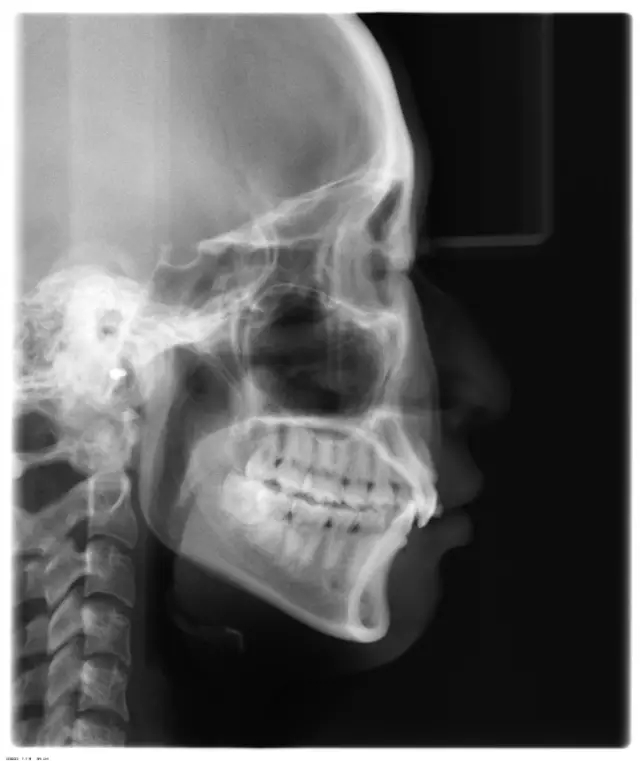

Damon 病例分享:安氏 II 類(lèi)二分類(lèi)露齦笑的矯治(董一磊)

患者信息